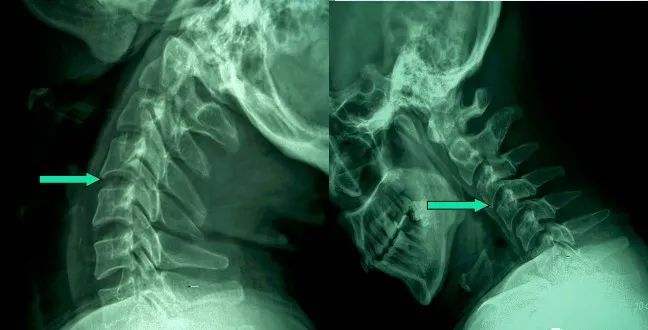

1、頸椎移位

頸椎移位

由于頸椎關(guān)節(jié)突間關(guān)節(jié)面近乎水平位,一旦椎間盤發(fā)生退變、椎間隙即變窄,關(guān)節(jié)囊及韌帶松弛,加上頸部活動(dòng)時(shí)重力的影響,即可造成積累性損傷,加速頸椎退變和不穩(wěn),導(dǎo)致頸椎關(guān)節(jié)發(fā)生移位,使椎間孔變狹,椎管徑發(fā)生改變,壓迫神經(jīng)根或脊髓,產(chǎn)生臨床癥狀與體征。